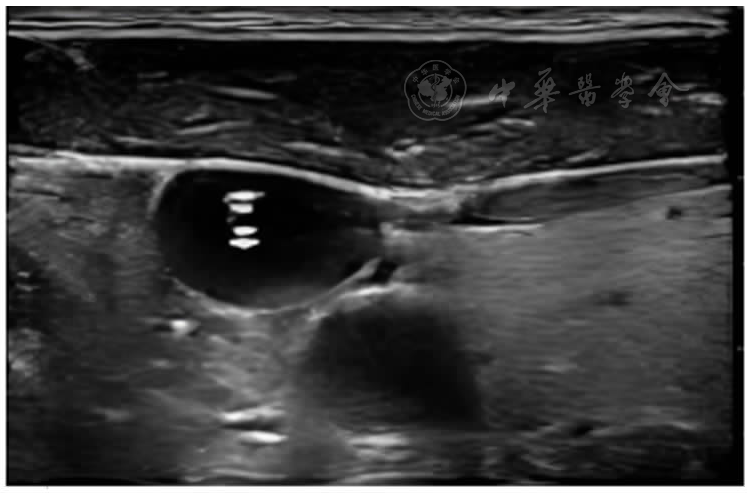

图3 胸片检查导管位置

图4 超声定位导管尖端位置